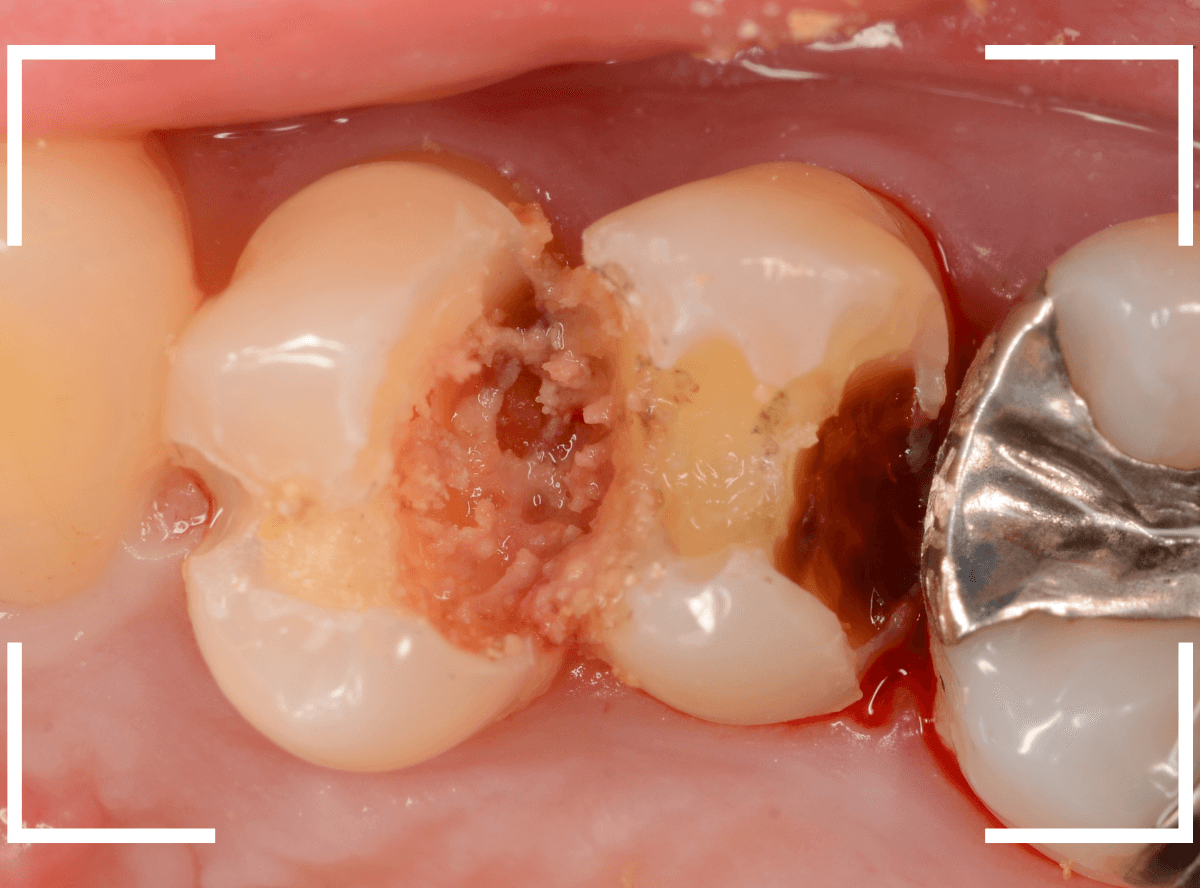

Case.19 神経まで達する大きな虫歯

「歯に違和感がある」という訴えで来院された患者さんです。

後ろの歯との間にぽっかり穴が開いているのがわかります。

このような場合、大抵は中で大きな虫歯になっています。

レントゲン写真で確認します。

青い部分が歯の神経、赤い部分が虫歯です。

レントゲン写真では、手前の歯との間も大きな虫歯になっているのがわかります。

そして、前後ともに神経まで達してしまっている虫歯に見えます。

治療を開始します。

少し削ったら、予想どおり大きな虫歯が出てきました。

虫歯が深いので、いつも以上に慎重に治療をすすめます。

赤くう蝕検知液で染まっている部分が虫歯です。

手前側は珍しく、レントゲン写真から予想される虫歯よりも小さかったです。

全ての虫歯を除去したところです。

やはり虫歯は大きく、歯の神経が一部露出する状況でした。

神経の中には血管もつまっていますので、出血するわけです。

神経を残せる可能性は半々といったところですが、神経を保護するお薬をつめた上にセメントで蓋をしました。

これでお痛みが出ないか、しばらく経過観察が必要です。